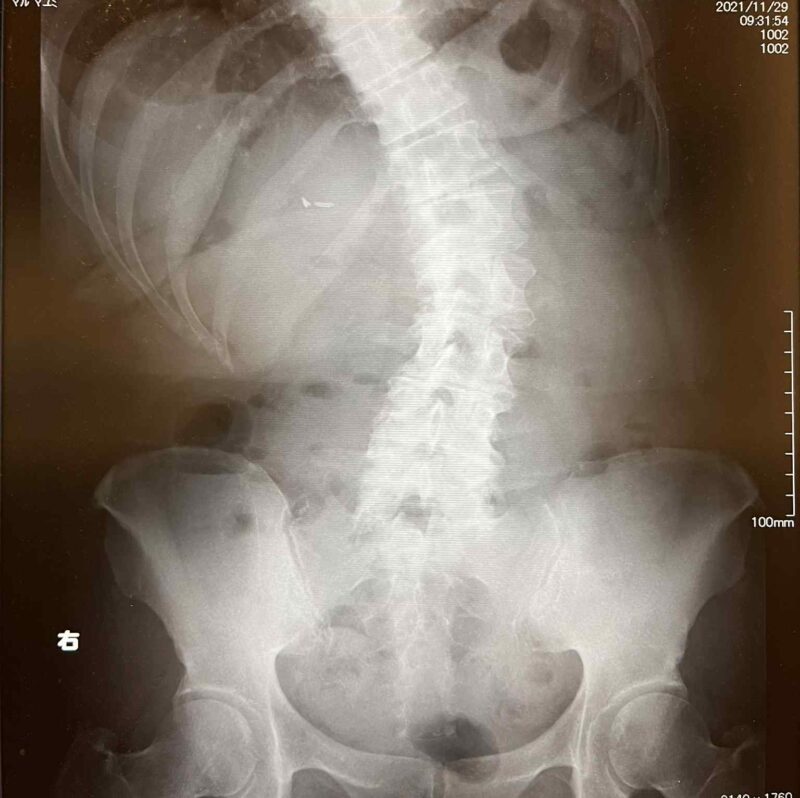

2021年に脊柱側弯症と診断され、同年12月からリハビリ開始。

2021年の8月末くらいから、なんとなく背骨が右に傾いているような気がしていたんです。

家族からも「おかしいな」と言われていて、それがだんだんひどくなり、

2021年の年末には歩くのも大変になってしまいました。

さすがに困ってきたので病院に行ったところ、脊柱側弯症であることが分かりました。

当時の丸さんの印象は、右手で杖をついて、ちょうど頭が右に傾いている状態でした。

背中も丸くて、とてもつらそうで、歩くのもゆっくり。

左足でバランスを取っているような、杖と右足に頼っている歩き方でした。

どれだけ背骨が曲がっているのか、

頭の位置が肩に対してどのあたりにあるのか、

足元を見たら顔の下にどちらの足が見えるのか、など、

背骨が右に傾いている状態だったので、

右と左で基本姿勢が大きく違っていて、

身体が右に傾き、左側の肋骨が開いて右側が狭くなっている状態だったので、

整形外科の先生にも、「明らかに良くなっていますね」と言われました。

何度もレントゲンを撮る必要はもうないだろう、

これ以上大きな変化はないかもしれないけれど、

この状態を維持していきましょう、と。